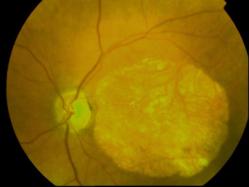

CICATRICE APRES EXERESE CHIRURGICALE DE NEOVAISSEAUX

IM000008.JPG